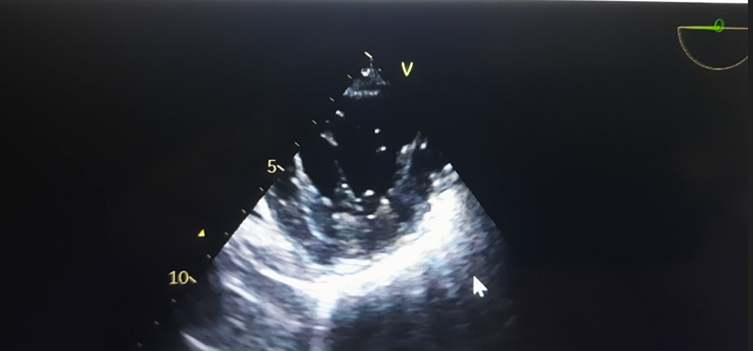

PCWP also revealed a large A wave suggestive of mitral regurgitation. A gastric tube was inserted to aspirate the stomach secretions and air and removed, and an adult TEE probe (GE, 6TC-RS, Vivid T9 v205, Norway) was inserted. Anesthesia was maintained with 60% oxygen in the air, sevoflurane 0.75- 1.5 % and vecuronium infusion (2mg/hr) with intermittent fentanyl and midazolam boluses. [9] She was positioned prone for the surgical procedure. External defibrillator pads were applied before turning the patient prone, and all resuscitation and antiarrhythmic drugs were kept ready to tackle an inadvertent arrhythmic event. The TEE was performed in the supine position and continued in the prone position with a little technical difficulty. TEE revealed an EF of 36%, fractional shortening (FS) of 17 Percent sign after inodilator support, severe MR with central jet, MR flow velocity > 5 m/sec and vena Contracta of 0.8mm(Figure 3a,b) and CO of 2.65 L/M2, mitral valve area of 4.3cm2 by planimetry, LA -31mm. (Figure 4) In addition LV basal wall aneurysmal, hypokinesia of basal, posterior and inferior LV wall, and no thrombus in LV(Figure 5a,b) and LV type 1, diastolic dysfunction (E Less-than sign)

HR-heart rate, BP-blood pressure, MAP- mean arterial pressure, SPO2- arterial oxygen saturation, PAP-pulmonary artery pressure, CVP- central venous pressure, PCWP- Pulmonary Capillary Wedge Pressure, MPAP- mean pulmonary artery pressure, SVR- systemic vascular resistance, CO- cardiac output, PVR- pulmonary vascular resistance, EF- ejection fraction, RA- room air, SvO2- mixed venous oxygen saturation PCWP also revealed a large A wave suggestive of mitral regurgitation. A gastric tube was inserted to aspirate the stomach secretions and air and removed, and an adult TEE probe (GE, 6TC-RS, Vivid T9 v205, Norway) was inserted. Anesthesia was maintained with 60% oxygen in the air, sevoflurane 0.75- 1.5 % and vecuronium infusion (2mg/hr) with intermittent fentanyl and midazolam boluses. [9] She was positioned prone for the surgical procedure. External defibrillator pads were applied before turning the patient prone, and all resuscitation and antiarrhythmic drugs were kept ready to tackle an inadvertent arrhythmic event. The TEE was performed in the supine position and continued in the prone position with a little technical difficulty. TEE revealed an EF of 36%, fractional shortening (FS) of 17 Percent sign after inodilator support, severe MR with central jet, MR flow velocity > 5 m/sec and vena Contracta of 0.8mm(Figure 3a,b) and CO of 2.65 L/M2, mitral valve area of 4.3cm2 by planimetry, LA -31mm. (Figure 4) In addition LV basal wall aneurysmal, hypokinesia of basal, posterior and inferior LV wall, and no thrombus in LV(Figure 5a,b) and LV type 1, diastolic dysfunction (E Less-than sign

Figure-6: Mitral inflow velocity revealed E wave < A>

In addition, the perioperative hemodynamic parameters and cardiac functions and volume status were also assessed using IVC size (1.7 cm) with >50% collapsibility in inspiration, biventricular filling and CO, which remained stable throughout the procedure and the heart rate was maintained between 80-90 beats/min in view of severe MR. TEE also confirmed the improvement in LV contractility and EF following the administration of dobutamine and NTG. Table -1 and (Figure 5b-video 1) The intraoperative ABG analysis revealed a pH- 7.31, PCO2- 51 mmHg, Pao2- 118 mmHg, SaO2 99%, Na+ -135 mmol/L, K+ 4.5meq/l, Ca+ 0.89mmol/L, glucose-118mg/dl, Hct- 46%, HCo3- 21.9mmol/l, BE-8.4 mmol/l and the values were acceptable in view of the COPD. The procedure lasted for 6hrs. Total blood loss was 450 ml, and 1.5 L of normal saline and one unit of fresh packed red blood cell transfusion were given, and total urine output was 1.5 L. At the end of the surgery, she was turned to supine, the neuromuscular block was reversed with standard doses of neostigmine and glycopyrrolate and she also required sugamadex (100 mg) for complete recovery and was smoothly extubated in OR. Inotropes were continued and tapered slowly over 6-8 hours and PAC was also removed in the PICU after 2 hours but the sheath was left in situ. Postoperative multimodal pain management was achieved using tramadol, i.v. paracetamol (1gm), fentanyl (25 mcg) boluses, transdermal buprenorphine patch (5mg). The patient was observed overnight in the postanaesthetic care unit and discharged on the 7th postoperative day with the instructions to attend the OPD for follow-up after one week.